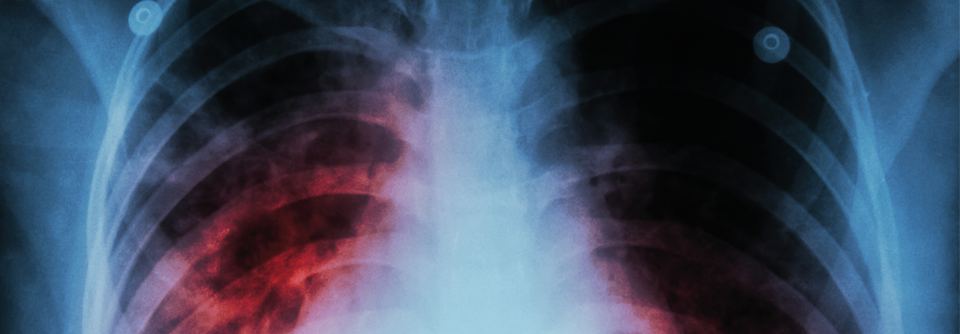

Pulmonale Erkrankungen aufgrund einer Infektion mit nicht-tuberkulösen Mykobakterien (NTM) sind in manchen europäischen Ländern schon häufiger als Tuberkulosefälle. Pulmonale Erkrankungen aufgrund einer Infektion mit nicht-tuberkulösen Mykobakterien (NTM) sind in manchen europäischen Ländern schon häufiger als Tuberkulosefälle. © 7activestudio - stock.adobe.com

Pulmonale Erkrankungen aufgrund einer Infektion mit nicht-tuberkulösen Mykobakterien (NTM) sind in manchen europäischen Ländern schon häufiger als Tuberkulosefälle, berichtete Prof. Dr. Dr. Christoph Lange vom Deutschen Zentrum für Infektionsforschung in Borstel. In Borstel wurden zuletzt insbesondere NTM-Infektionen mit der M. avium intracellulare-Gruppe (MAC), M. gordonae und der M. abszessus/M. immunogenum-Gruppe registriert. Risikofaktoren für eine pulmonale NTM-Infektion sind pulmonale Vorerkrankungen wie Bronchiektasen, eine frühere pulmonale Tuberkulose oder eine COPD, aber auch inhalative Kortikosteroide, ein hohes Lebensalter, Diabetes mellitus, Alkoholabusus und Rauchen.